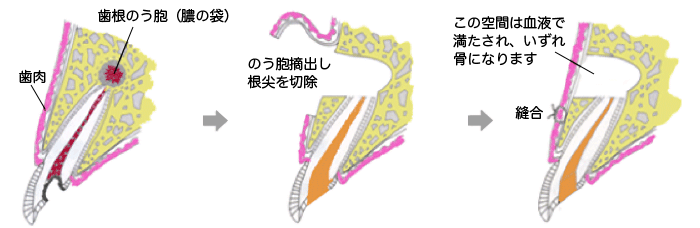

歯内療法外科

歯根の先に膿が溜まったとき、根管治療を行っても治らない場合は歯内療法外科を行います。通常は歯肉を切開して病巣を取り除きますが、原因である根管内の感染がなくならないかぎり、抜本的な解決にはならないため、根管治療と併せた処置が必要です。

歯根端切除術

根管治療が奏功しなかった場合、歯根の先端に膿の袋(根尖病変)が形成されることがあります。膿の拡がりが大きい場合には抜歯が検討されることもありますが、病変が限局しているケースでは、外科的に根尖部を切除し、同時に膿の袋を摘出する「歯根端切除術」によって、歯を保存することが可能です。

この処置には高度な技術が求められますが、適応症例を正確に見極めたうえで行うことで、機能回復と歯の延命が期待できます。